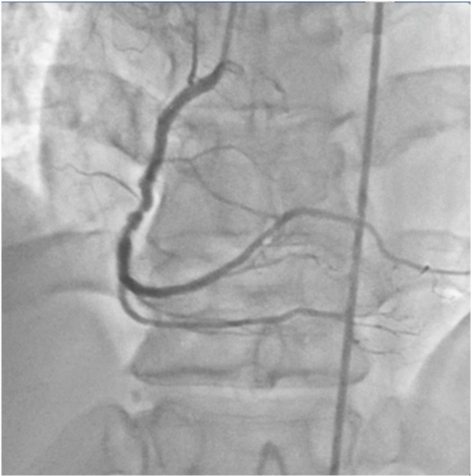

A check shot done at this stage of the procedure demonstrated fully expanded LM-LAD and LCX stents with brisk TIMI 3 flow into both arteries, but large fragments of thrombi appeared in the LAD artery (Figure 10), (Video 3) The patient complained of chest discomfort and this was accompanied with slight lowering of heart rate and drop in blood pressure. An intra-coronary (IC) bolus injection of tirofiban (20mcg/Kg) was immediately administered and this rapidly completely lysed the thrombi in the LAD artery (Figures 11 & 12), (Video 4). The patient was shifted to the CCU on intra-venous tirofiban infusion for the next 18 hours. His further stay in hospital was unremarkable, and he was discharged on the third day in stable condition on aspirin, prasugrel, atorvastatin, ramipril and metoprolol.

Figure 11 Fully expanded ( angiographically) stents in LM-LAD and LCX arteries, with TIMI 3 flow and no dissection.

Figure 12 Fully expanded LM-LAD and LCX stents with brisk TIMI 3 ante grade flow in both arteries.